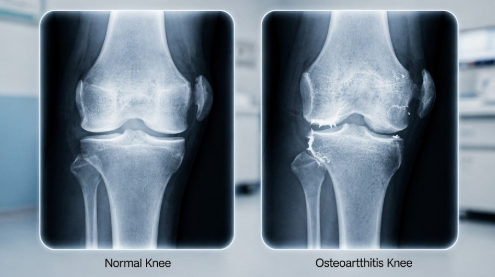

7. 관절 변형 (눈으로 보이는 변화)

질환이 진행되면 관절 모양이 눈에 띄게 변할 수 있습니다. 손가락 마디가 두꺼워지거나 무릎이 휘는 경우가 대표적입니다.

이러한 변형은 단순한 외형 변화가 아니라 기능 저하로 이어질 수 있습니다.

9. 퇴행성 관절염 진행 단계

퇴행성 관절염은 다음과 같은 단계로 진행됩니다.

- 1단계: 가벼운 통증, 간헐적 불편감

- 2단계: 활동 시 통증 증가, 소리 발생

- 3단계: 지속적인 통증, 움직임 제한

- 4단계: 심한 통증, 관절 변형 및 기능 저하

초기 단계에서 관리할수록 진행을 늦출 수 있습니다.